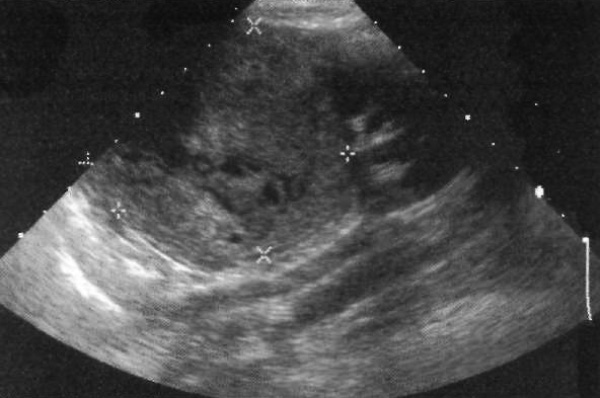

Нефробластома (опухоль Вильмса) – злокачественное образование из зародышевых клеток, развивающаяся в раннем детстве (пик развития заболевания наблюдается в 3-летнем возрасте). На УЗИ в зоне поражения визуализируется крупное образование неоднородной эхоструктуры (фото 7). На периферии может определяться поясок пониженной или повышенной эхогенности – ложная капсула. При этом нужно проверить ультразвуковые симптомы распространения опухоли в ипсилатеральную почечную вену и далее – в нижнюю полую вену.

Фото 7. Нефробластома. Ультразвуковое изображение левой почки в продольной проекции 4-летней девочки: курсорами отмечено крупное гиперэхогенное образование, которое замещает верхнюю половину почки.